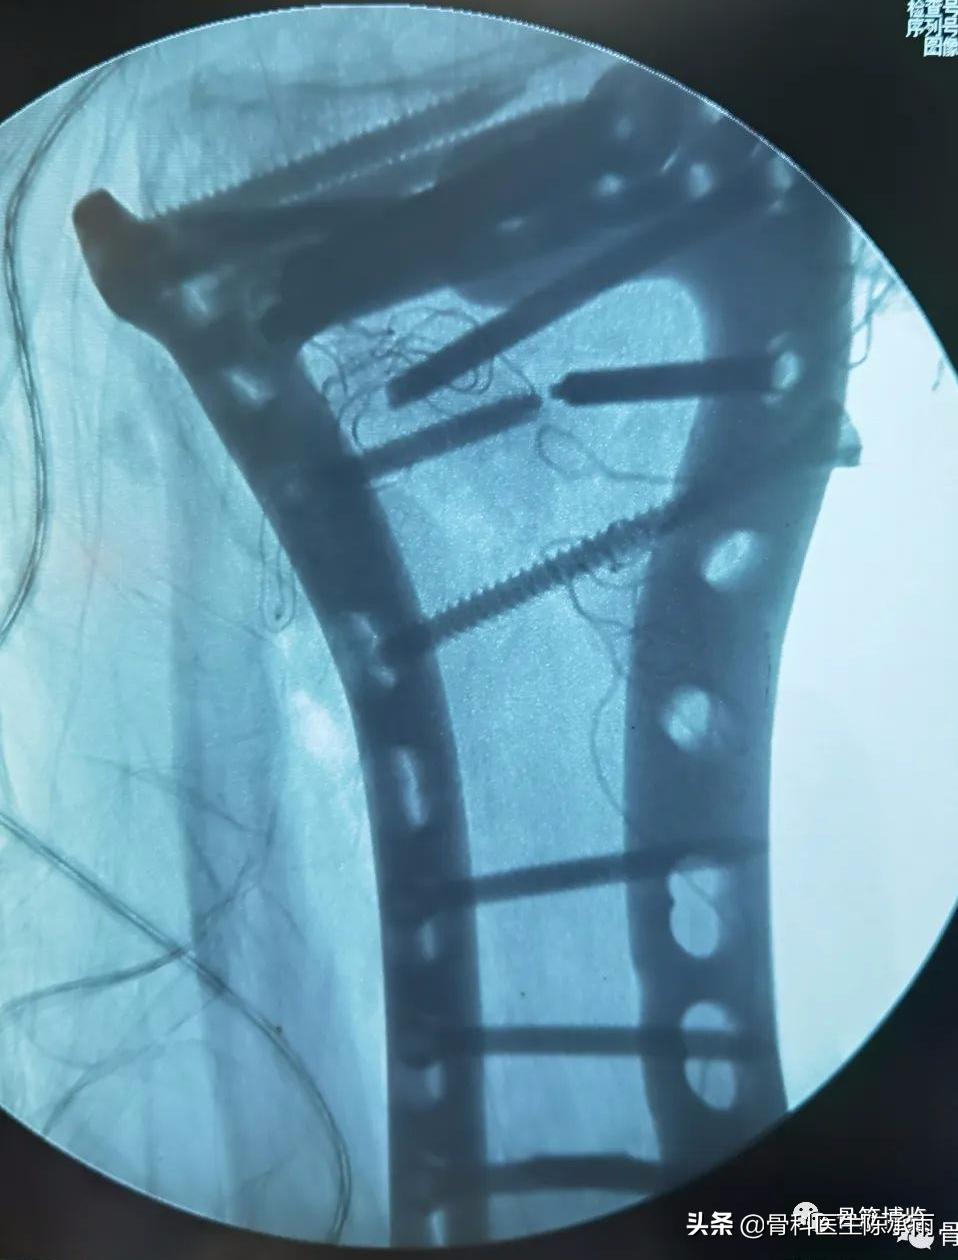

这2例患者皮肤条件差,全身多发骨折,小腿皮肤条件差,1例筋膜高压切开,1例整个小腿布满张力性水泡,胫骨骨折都在伤后30天才能手术。

下例胫平台骨折皮肤条件差,内侧板取两端小切口置入内板固定。胫骨结节处撕脱骨折以1枚拉力螺钉固定。